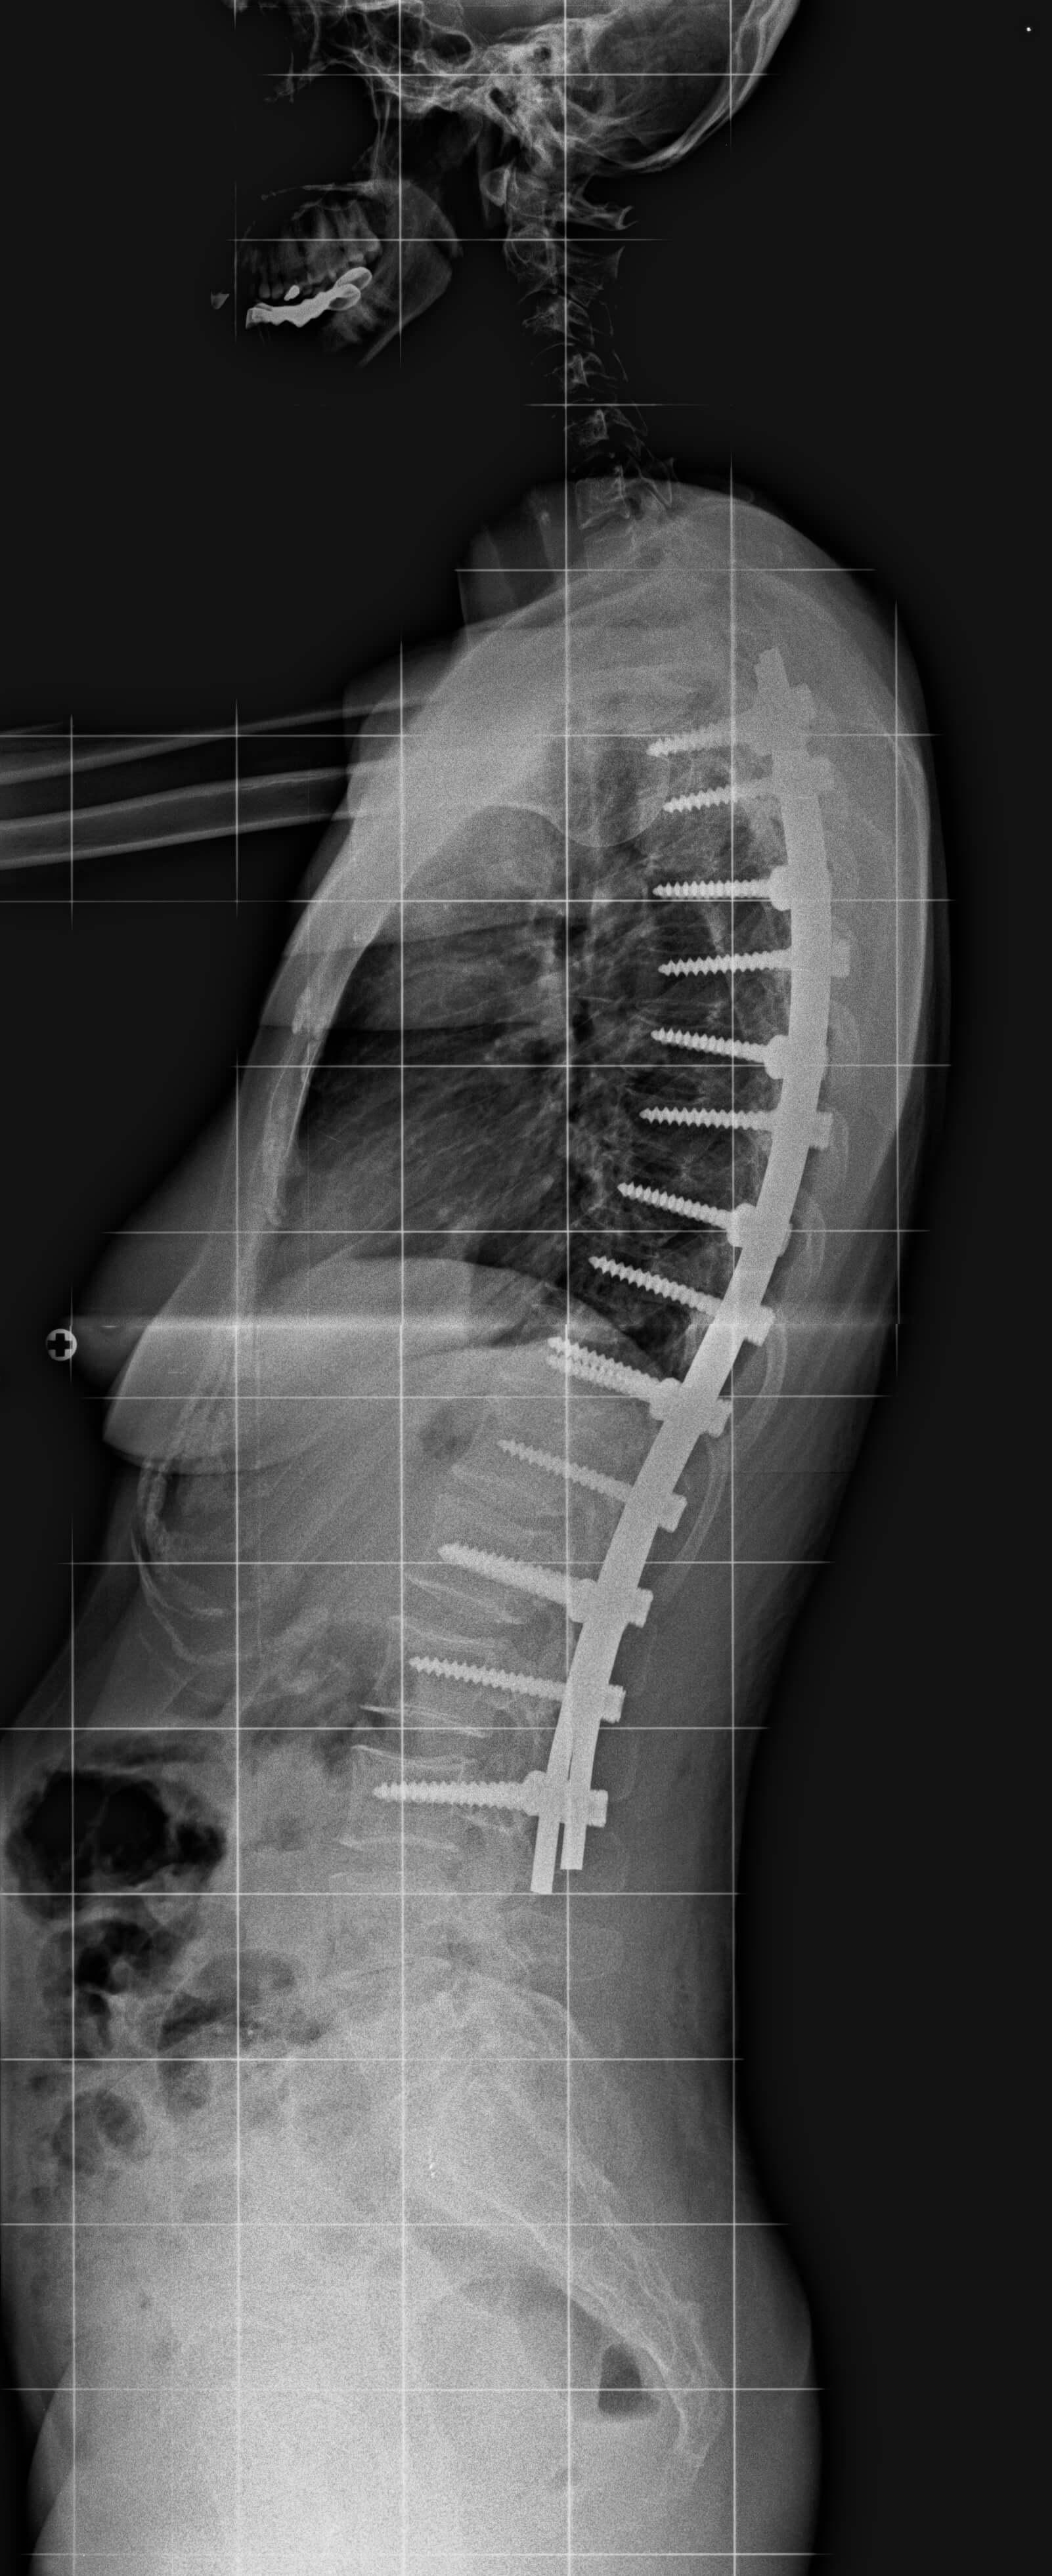

26 yaşında kadın hasta. Sırt ve bel ağrıları mevcut.

Ameliyat Sonrası